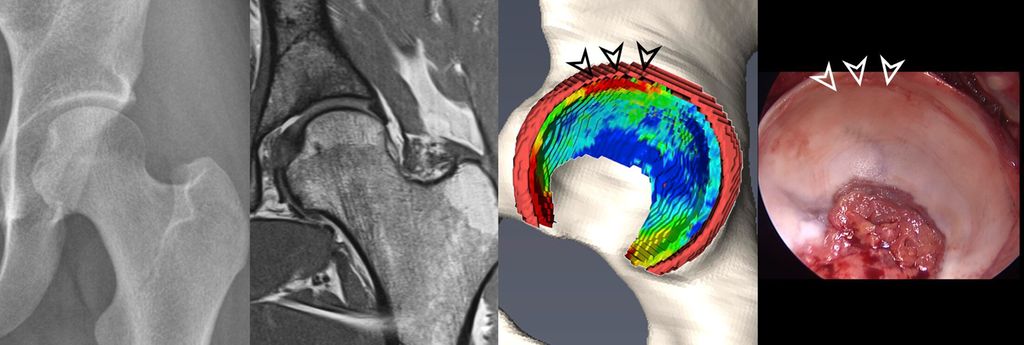

Fig. 1: Traction MR arthrography allows for better visualization of the opposing acetabular and

To improve visualization of the central joint cavity during MR arthrography, axial leg traction can be applied, similar to the joint distraction needed during hip arthroscopy (Fig. 1). Traction MR arthrography of the hip has shown high accuracy in detecting chondrolabral lesions, ligamentum teres injuries, and intra-articular loose bodies and has demonstrated its value in predicting failure of FAI surgery.5–8 It is particularly helpful for better visualizing the extent of cartilage damage in older patients with mild radiographic joint degeneration and thus aid in surgical decision making. Traction MR arthrography can also detect unstable labral tears in patients with hip dysplasia and may aid in planning treatment for femoral head necrosis in young patients with early collapse and preserved joint space.4

Fig. 2: 3D models of hip cartilage and labrum with color-coded dGEMRIC indices to visualize biochemical cartilage degeneration (red color, black arrowheads) which was confirmed during surgery (white arrowheads).